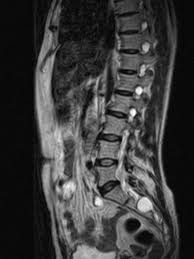

The mri will show whether a tumor is growing in or near the spinal column, or if another culprit is causing the pain—such as arthritis. A cancerous spinal tumor's rate of growth can vary depending on the type. I am 11 years free of 2a hodgkin lymphoma because of roswell. The cancer is approx 4.5cm and it has also spread a bit behind. You can have traditional iv chemo, with just a chest port. The diagnosis is accelerated today, dr. When the spine is not lined up properly, other physically notable symptoms may result (e.g., changes in posture, kyphosis or hunchback). The symptoms of spinal tumor can also progress slowly over a matter of weeks or years.

Get your mammograms, they can and will save your life. You can do nothing, but i don't recommend that. 4 signs of breast cancer that you've. Medical history and physical exam The mri will show whether a tumor is growing in or near the spinal column, or if another culprit is causing the pain—such as arthritis. How did i find out i had cancer. Baaj also serves on the. Ive had a cough for over a month,went to the docs,and its now accelerated to lung cancer.